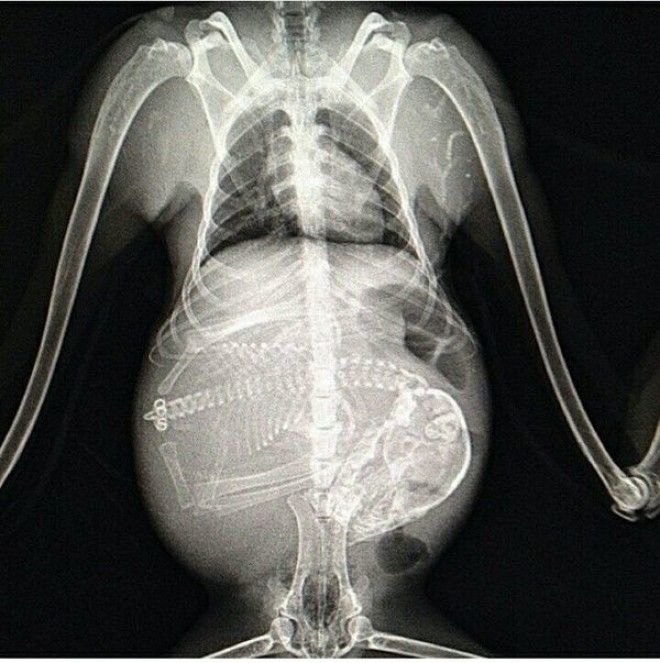

1. Беременная собака